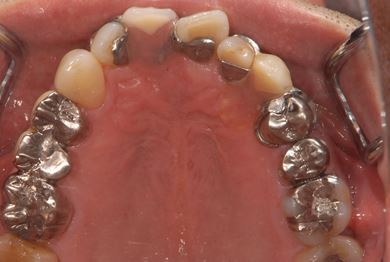

| 性別/年齢 | 男性 / 65歳 | ||||||||||||||||||||||||||||||||

| 主訴 | 右奥歯の義歯の不具合について相談したい。 | ||||||||||||||||||||||||||||||||

| 治療方針 | 抜歯と同時にインプラント埋入を行い、治療期間を短縮する。 | ||||||||||||||||||||||||||||||||

| 治療内容 | インプラント5本(抜歯即日スピードインプラント、テンポラリーインプラント)、メタルボンドセラミッククラウン5本 | ||||||||||||||||||||||||||||||||

| 総治療費 | 1,913,100円 | ||||||||||||||||||||||||||||||||

| 治療期間 | 1年9ヶ月 |